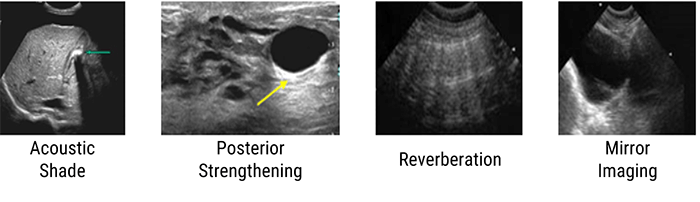

What is an Artifact? And what is the cause of getting an artifact in an ultrasound image?

Artifacts in Ultrasound Diagnostics are a reflection or echo that appears on the display and represents the actual structure of the anatomy incorrectly. An artifact may be false, multiple or misleading information introduced by the imaging system or by the interaction of ultrasound with the adjacent tissue.

Some artifacts have their origin in a wrong setting of the device. For example, an excessive level of amplification may reveal scattered echoes in a fluid-structure (bladder, artery) corresponding to an exaggerated amplification of the noise. Other artifacts are related to the nature of the interactions between ultrasound and tissue. We can mention these 4 main artifacts: The acoustic shade, the posterior strengthening, the reverberation, and the mirror imaging.

Acoustic Shade

The acoustic shadow phenomenon occurs whenever the ultrasonic beam is intercepted by a highly reflective structure. This is the case of bones, digestive gases, kidney stones, or gallstones. In this image, the reflecting wall is represented by a very intense echo behind, which is projected in a cone of acoustic shadow where no image is visible. This artifact aids in the identification of calculi and also prevents the examination of deeper structures.

Posterior Strengthening

The second artifact is the posterior reinforcement artifact, which often occurs when the echo passes through a fluid zone (cyst).

Reverberation

The third artifact is the reverberation artifact, which is related to the “trapping” of ultrasound waves between two reflective surfaces. These waves bounce between the surfaces, where at each bounce, a small echo is released to the probe and forms an image. This reverberation causes a repetitive artifact on the ultrasound image. The appearance of the reverberation artifact depends on:

- The size of the two reflective surfaces

- The distance between the two reflective surfaces (long vs short path reverberation artifacts)

- And how much ultrasound energy is dissipated or attenuated, between each re-reflection

Mirror Image

And finally, the mirror image is formed near a very reflective interface; it is observed mainly at the diaphragm. The ultrasound is reflected on the diaphragm towards the liver tissue and then they follow the opposite way. The ultrasound machine ignores this reflection and considers it as a rectilinear movement of the ultrasound.